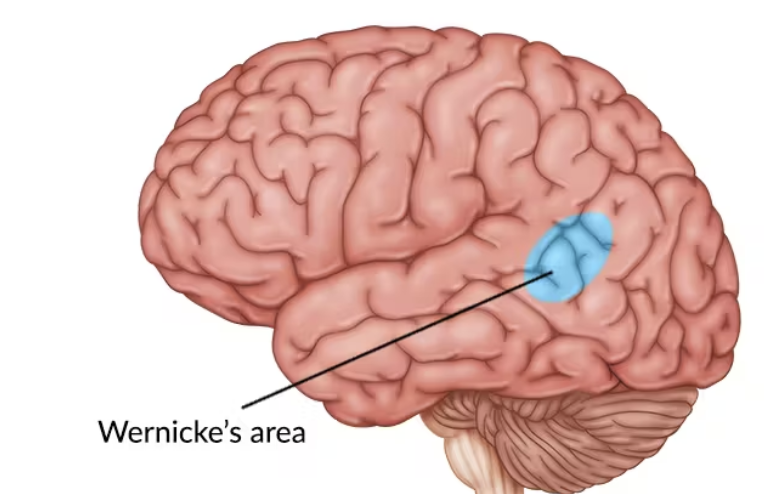

Which area is for language comprehension (receptive)?

Wernicke’s area